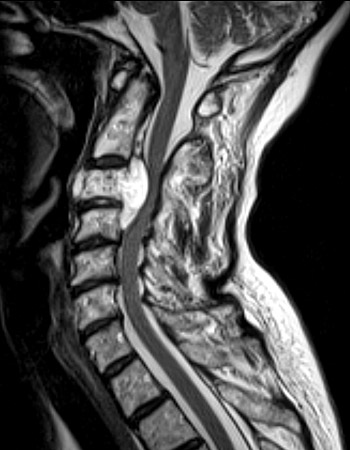

spinal imaging

T1: CSF dark, pathology often dark

T2: CSF bright, pathology often bright

STIR (short tau inversion recovery): T2 with suppression of fat